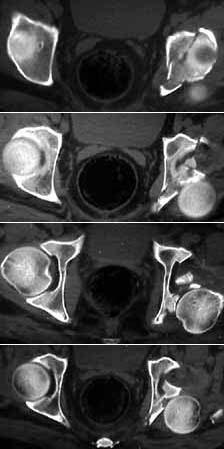

Seeking advice on management of 50 years old male who presented with infected fracture dislocation right hip with complete sciatic nerve palsy three months after injury. Xrays initial and current and CT scan Current images attached.

CT Scan

I am not certain why the hip is irreducible. The images show the femoral head completely posterior to the acetabulum with lots of bone fragments (presumably from posterior lip of acetabulum) anterior to the head nearly filling the acetabulum. You said bone fragments were removed. I would do whatever it took to reduce the head back into the socket.